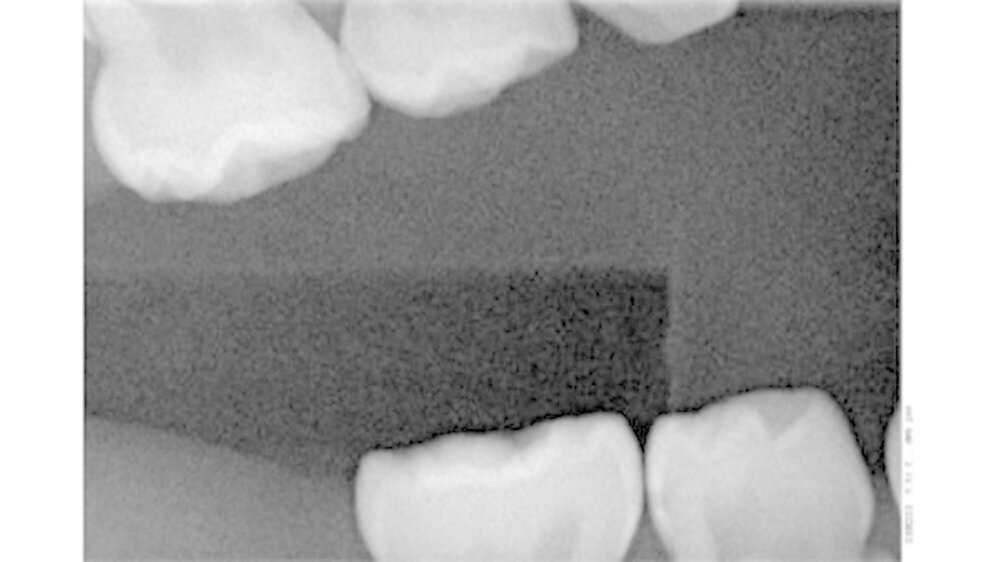

Wie wichtig ist die Bissflügelaufnahme für die Diagnose?

Ich mache immer mehr Bissflügelaufnahmen und immer früher. Denn erkenne ich eine initale Karies früh, kann ich diese mit den Eltern zusammen ausheilen, sprich eine Füllung beziehungsweise abhängig vom Alter und der Kooperationsbereitschaft des Kindes eine Sanierung in Narkose verhindern. Das Röntgenbild zeigt den Eltern das Problem und hilft mir, sie für die Verwendung von Zahnseide zu gewinnen.